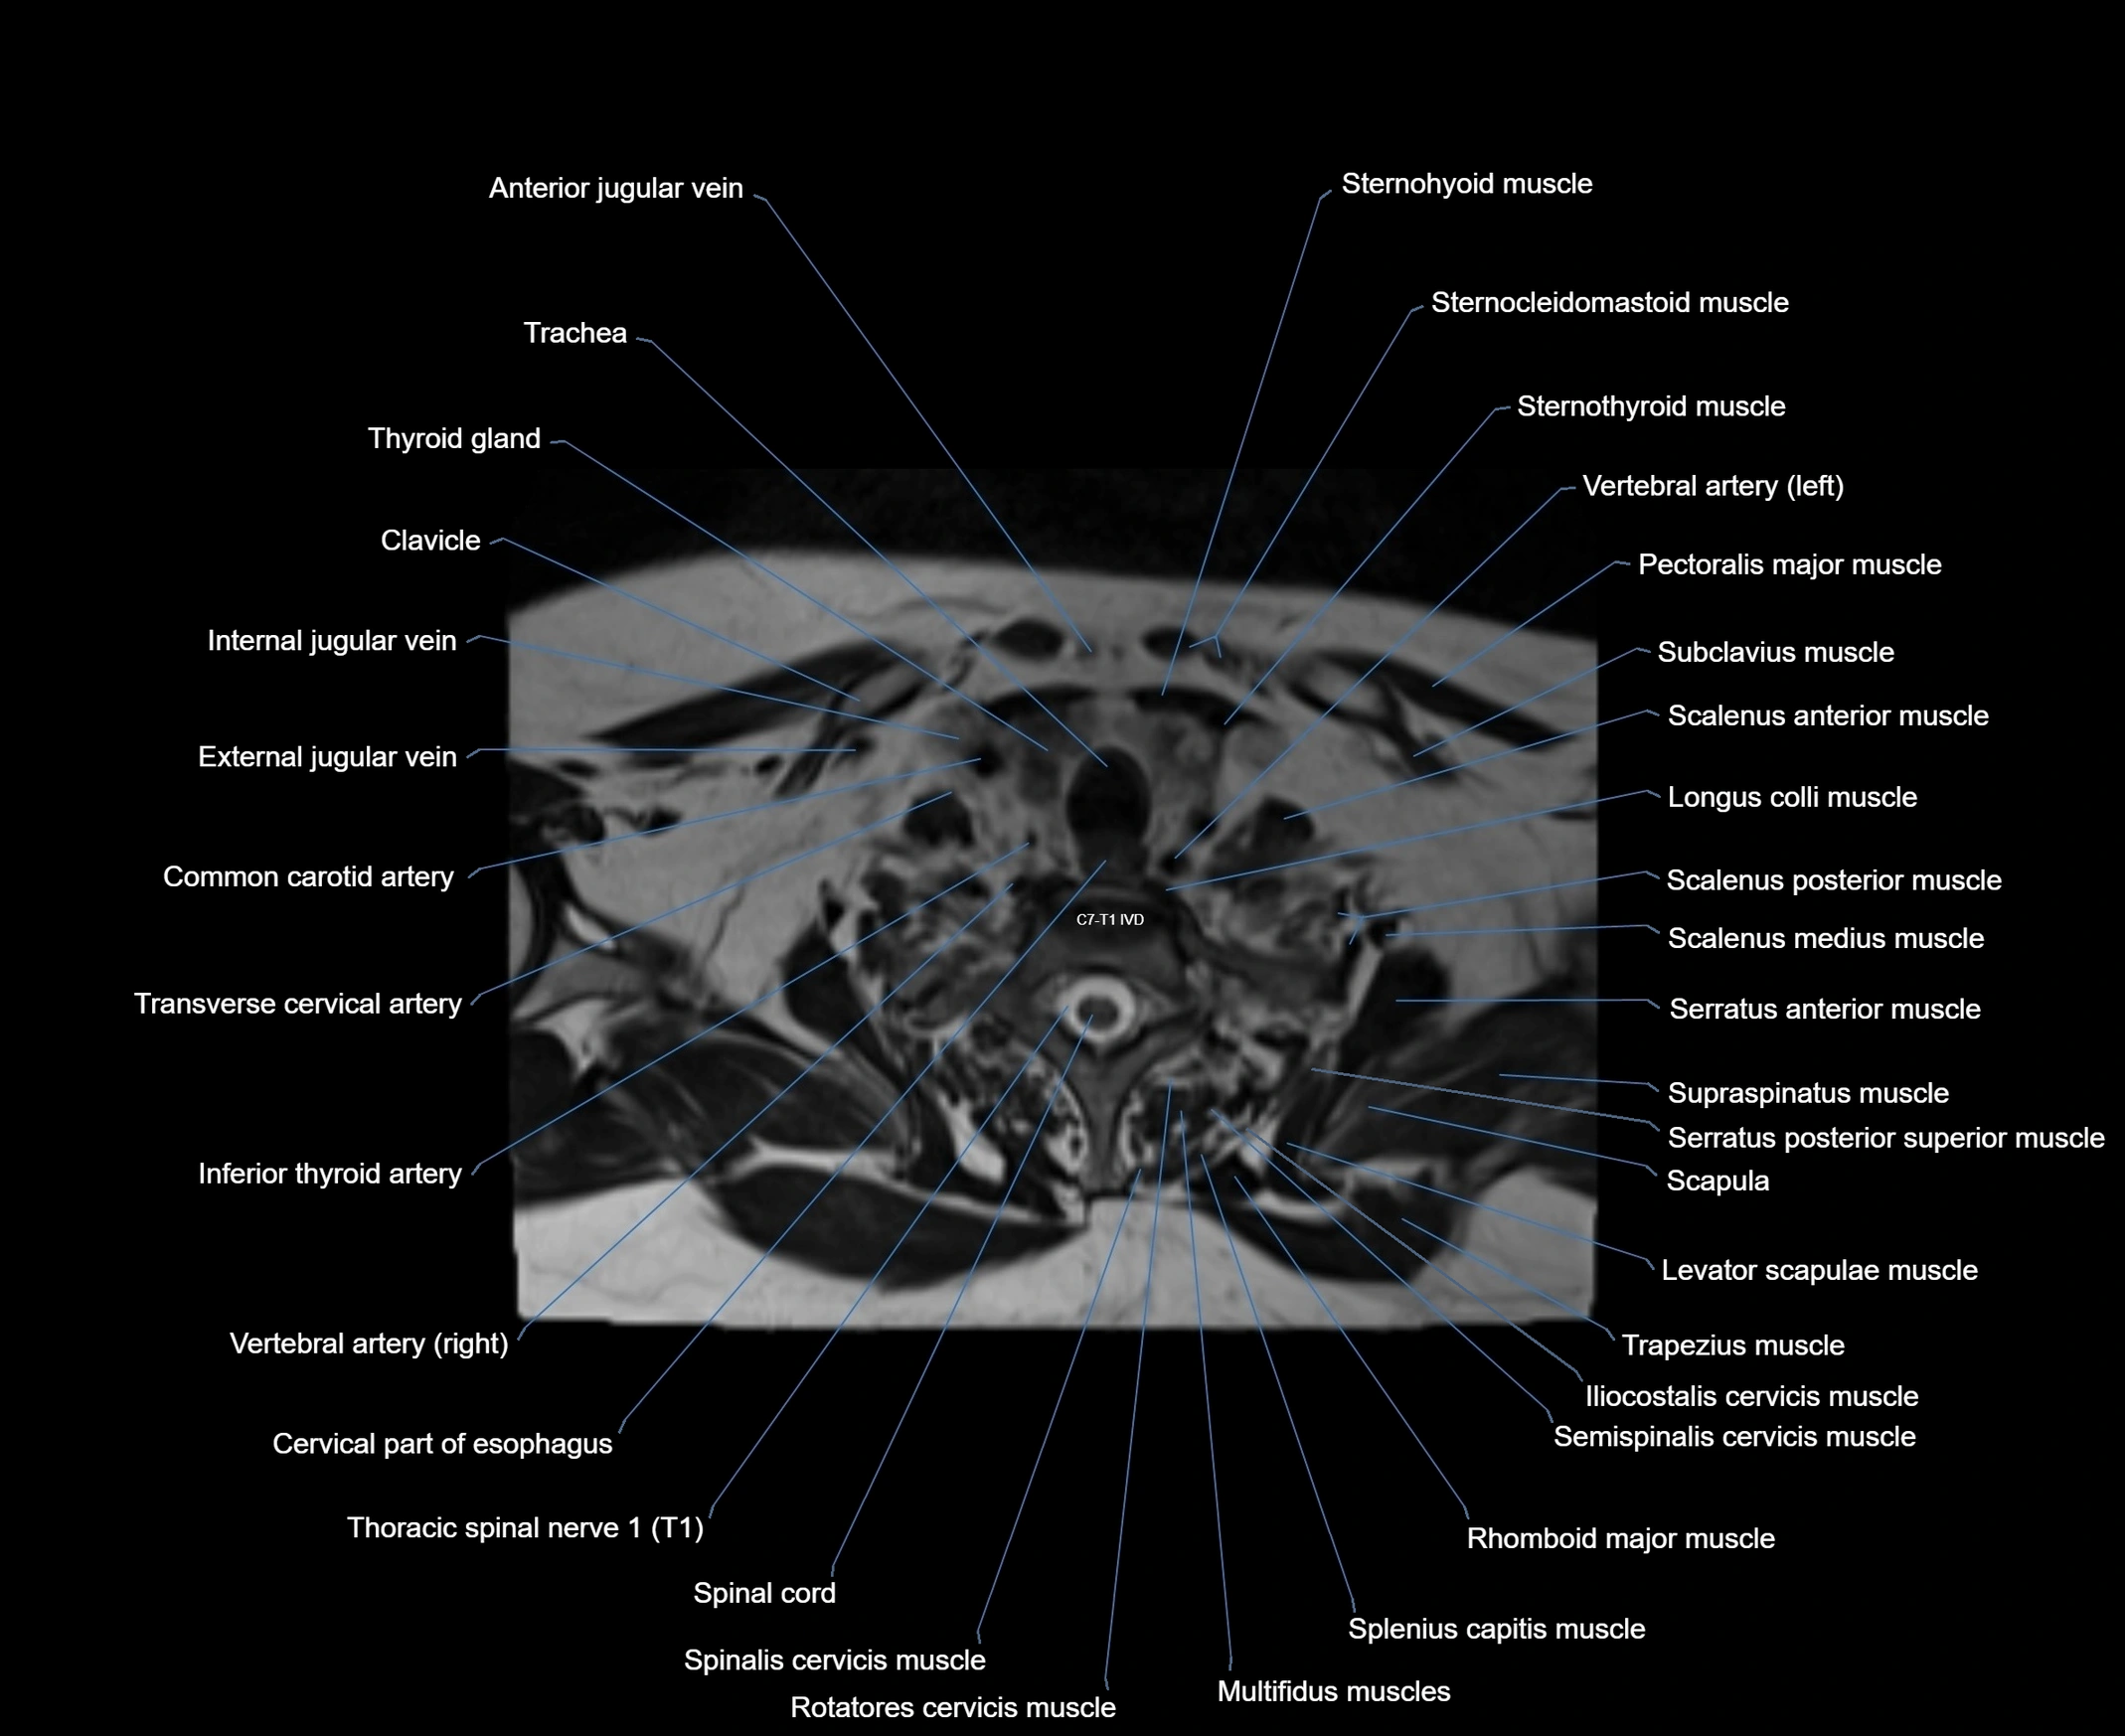

- Scalenus anterior muscle (Anterior scalene muscle)

- Scalenus medius muscle (middle scalene muscle)

- Scalenus posterior muscle (Posterior scalene muscle)

- Semispinalis cervicis muscle

- Spinal cord

- Spinalis cervicis muscle

- Rotatores cervicis muscle

- Multifidus muscles

- Rhomboid major muscle

- Supraspinatus muscle

- Serratus anterior muscle

- Serratus posterior superior muscle